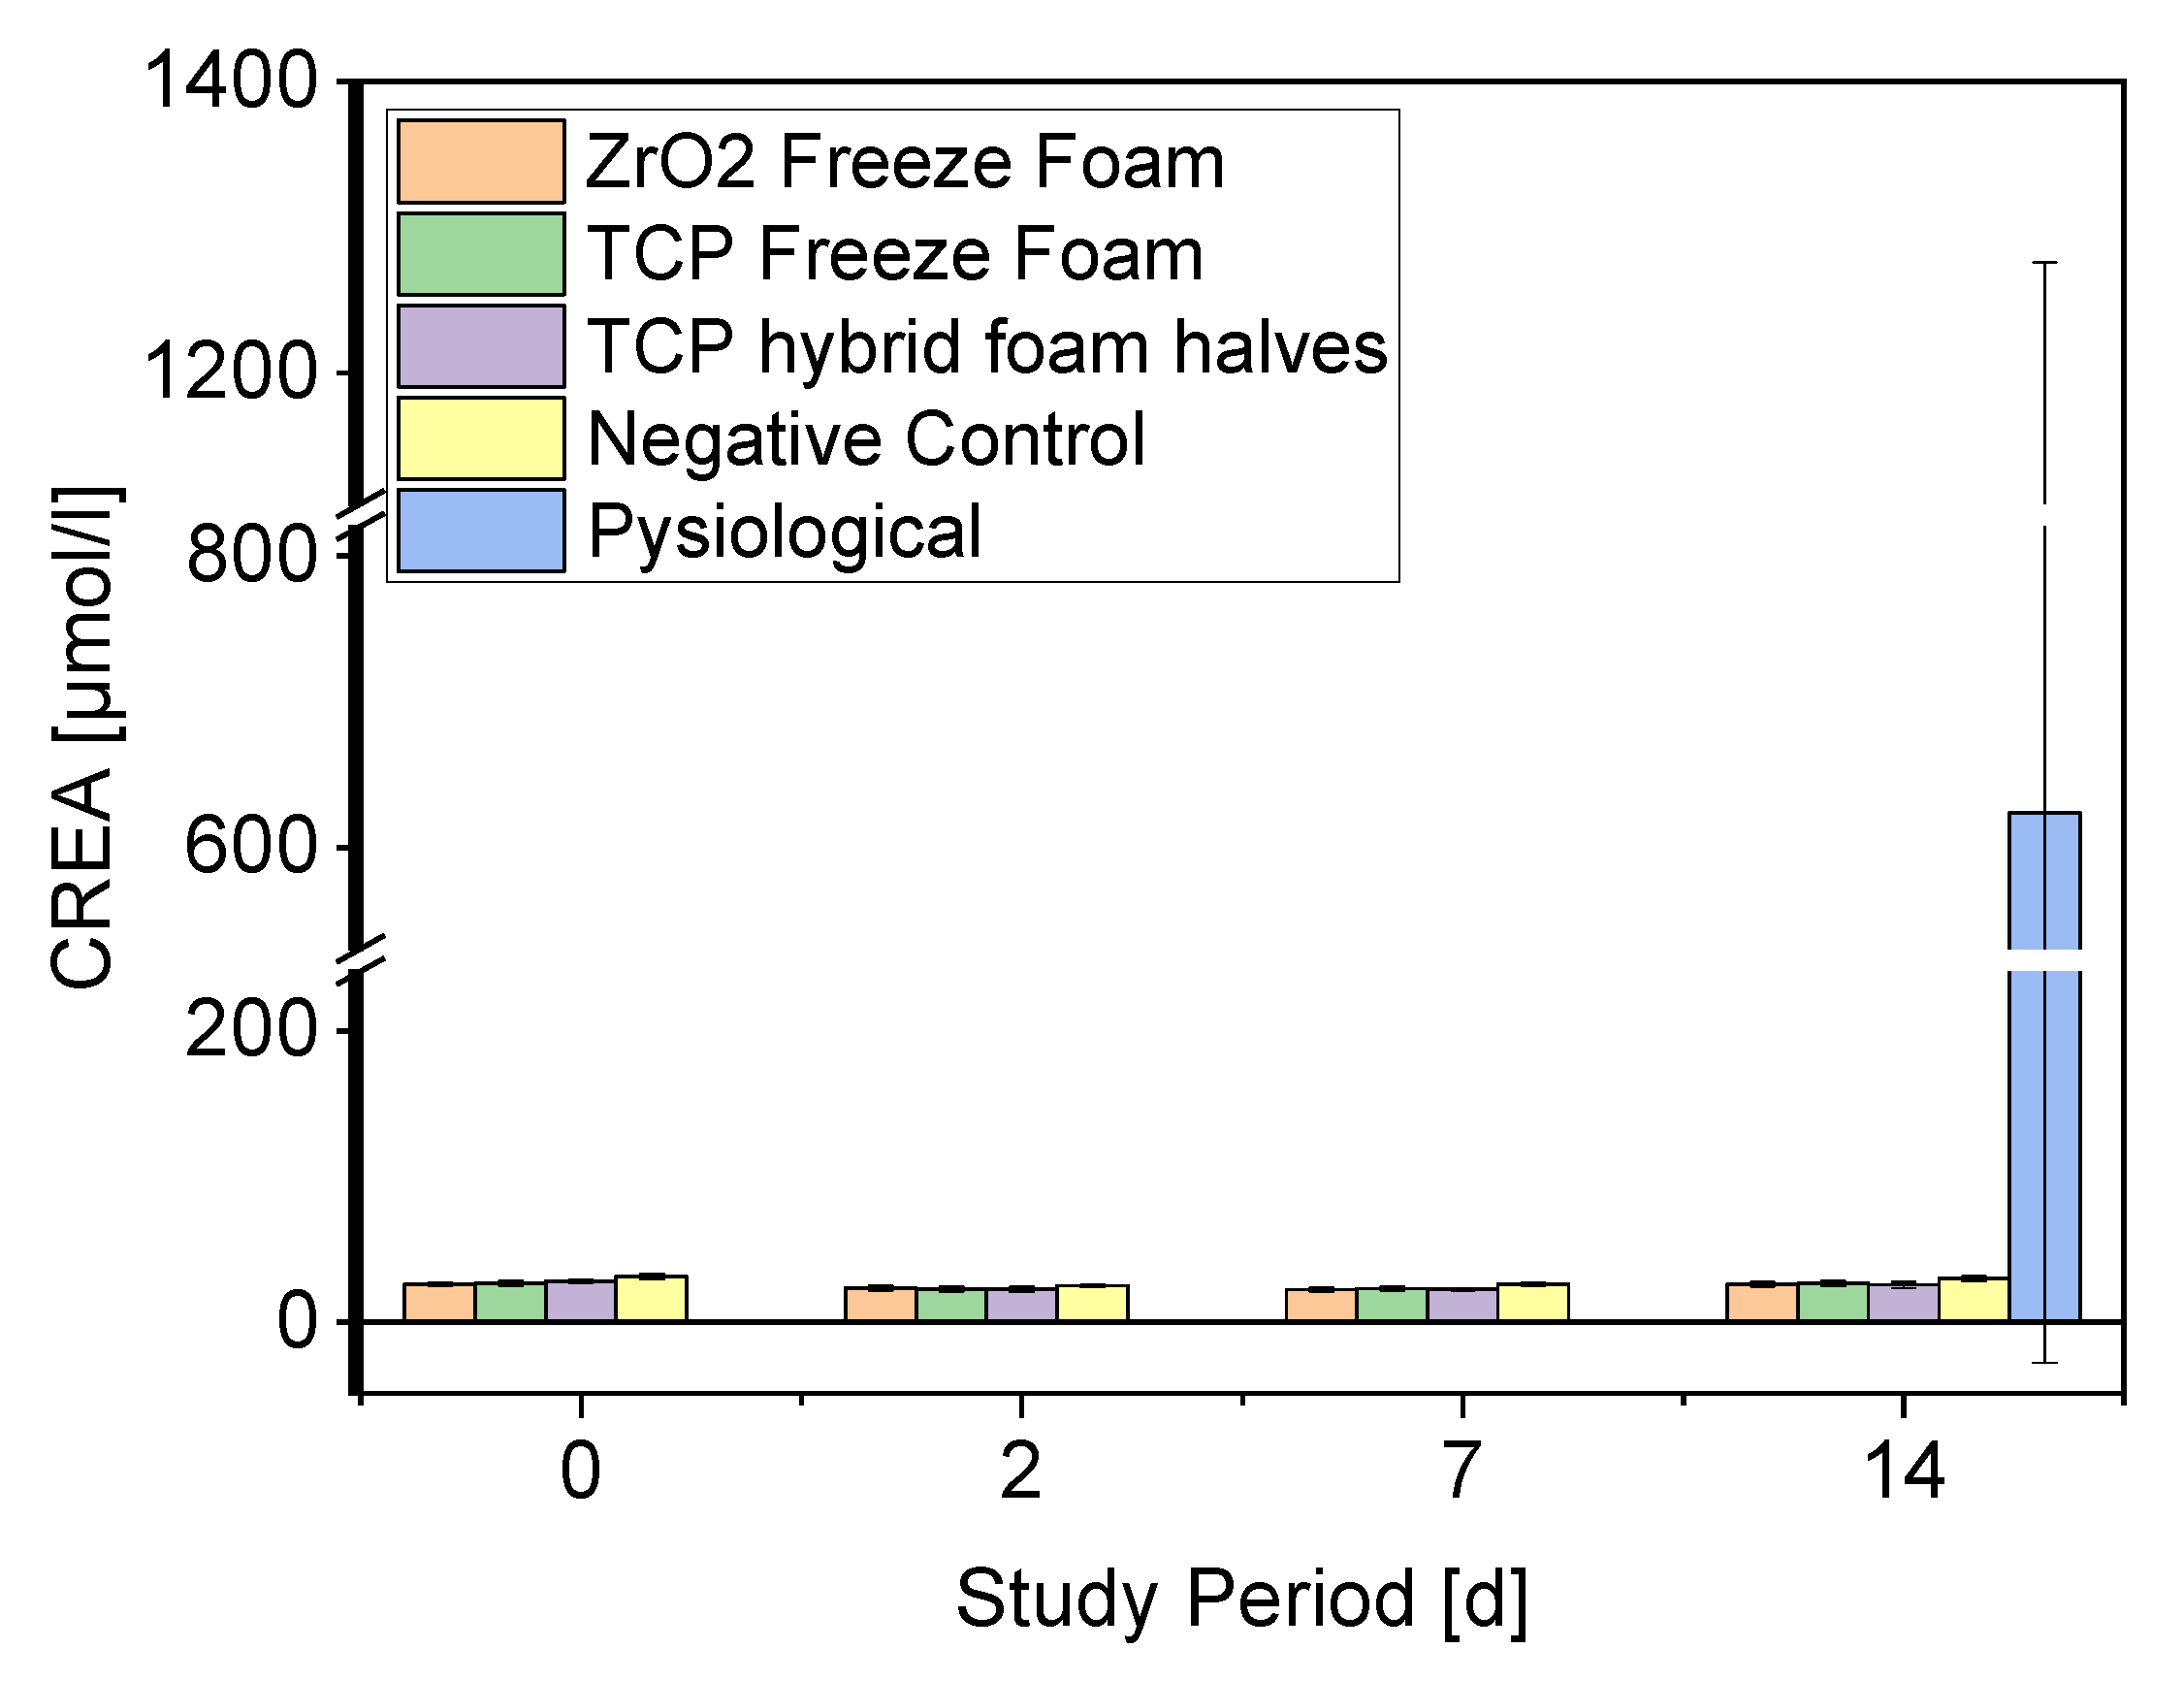

- Serum Parameters

3.4.2. Creatinine